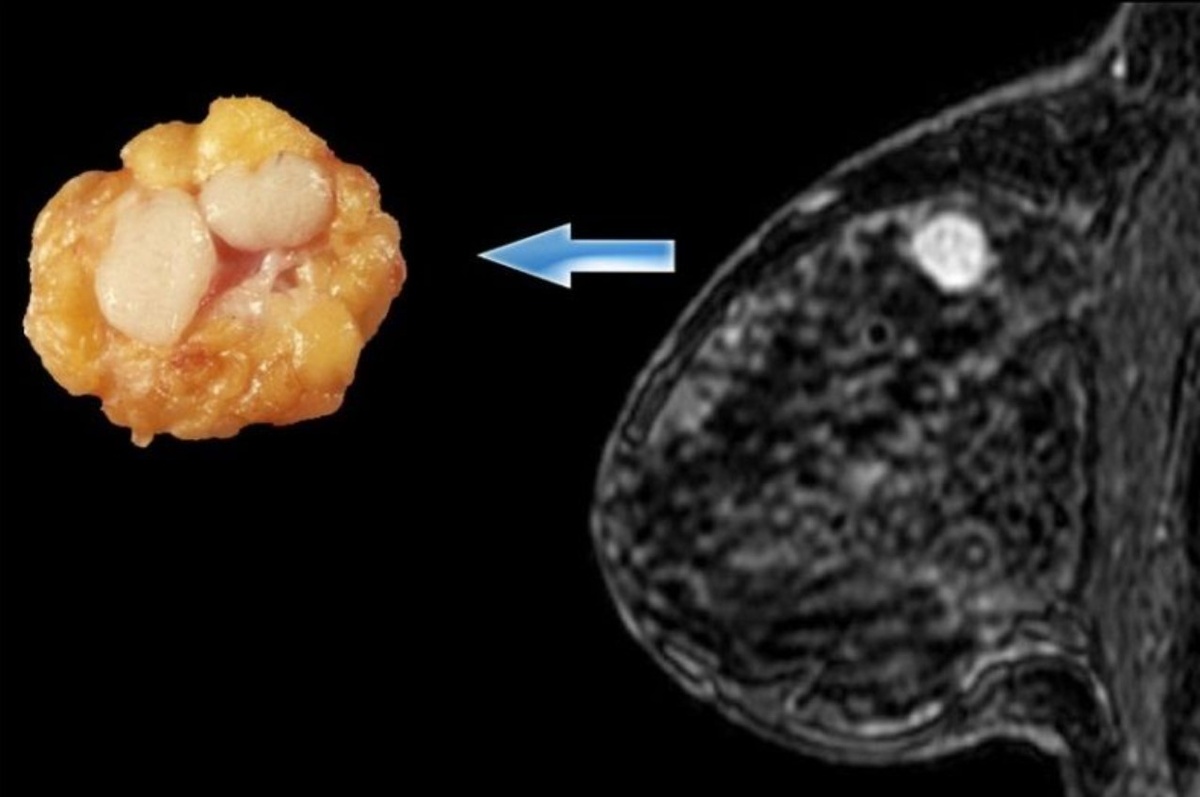

Важным направлением стало изучение ангиогенеза (роста сосудов). С помощью контрастного МРТ врачи 2026 года оценивают, насколько активно кровь поступает к участку уплотнения. Аномально быстрая «закачка» контраста в зону плотной кожи является важным биохимическим сигналом, требующим немедленного внимания.

• МРТ молочных желез с динамическим контрастированием: Самый точный метод для выявления связи между кожей и глубокими тканями.